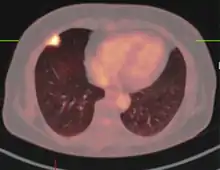

If there is an intermediate risk of malignancy, further imaging with positron emission tomography (PET scan) is appropriate (if available). It can be done simultaneously as a CT scan in the form of PET-CT. Around 95% of patients with a malignant nodule will have an abnormal PET scan, while around 78% of patients with a benign nodule will look normal on PET (this is the test sensitivity and specificity).[15] Thus, an abnormal PET scan will reliably pick up cancer, but several other types of nodules (inflammatory or infectious, for example) will also show up on a PET scan. If the nodule has a diameter of less than one centimeter, PET scans are often avoided because of an increased risk of falsely normal results.[15][16][17] Cancerous lesions usually have a high metabolism on PET, as demonstrated by their high uptake of FDG (a radioactive sugar).

PET-CT of a tuberculoma.